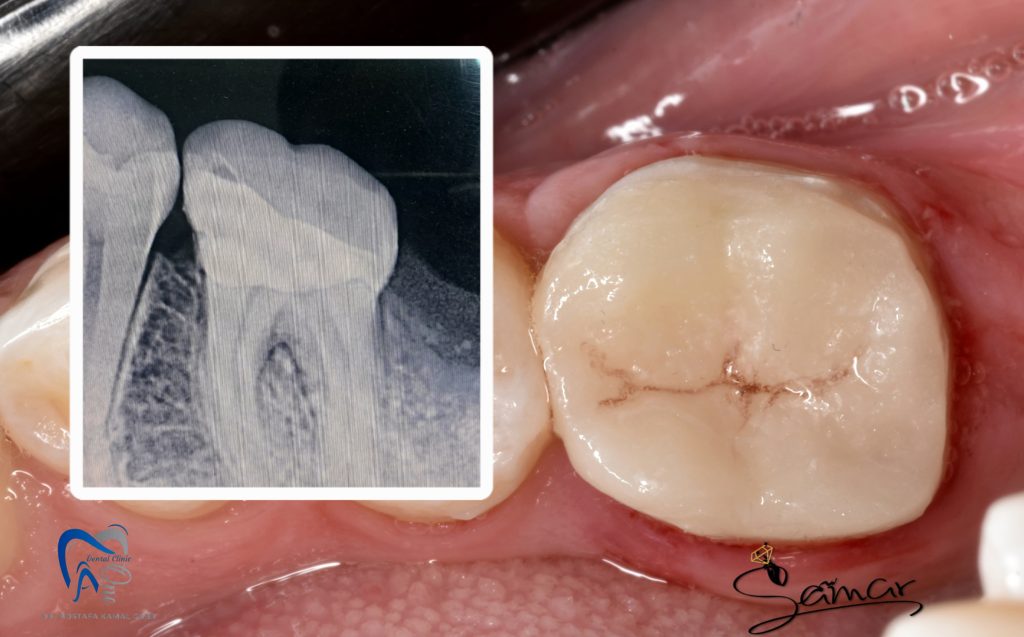

Final post operative and Radiograph veiw

Buccal view

pre and post periapical radiograph